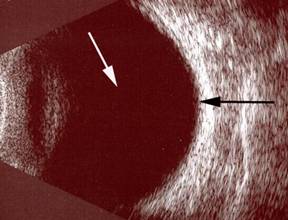

Resim 2: Yandaki resimde retinada dev yırtığın yukarıdan aşağıya doğru uzandığı, yerinden ayrılan retinanın üzerine katlandığı izlenmektedir (siyah ok).

Resim 3: Normal göz ultrasonografi görüntüsü. Gözün arkasını dolduran göz sıvısı (vitreus) beyaz okla, retina tabakası siyah okla gösterilmektedir.